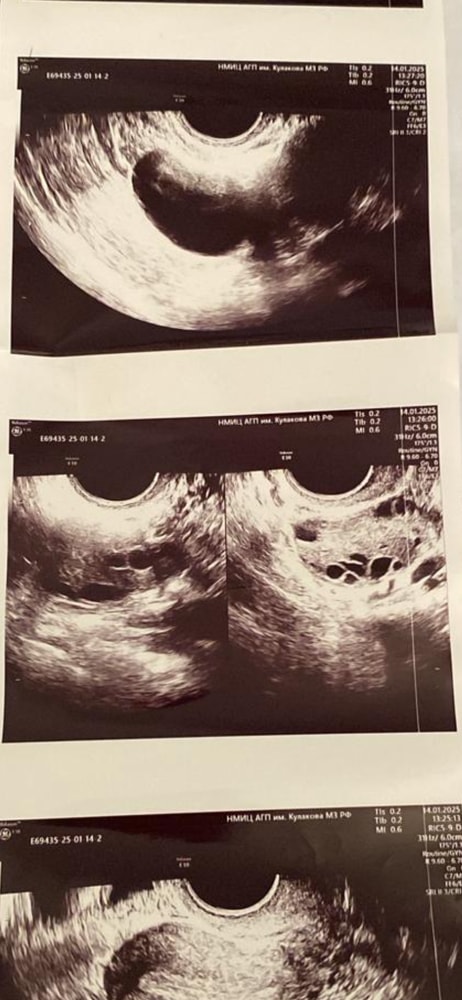

Ольга, РазмерыДлина: 46 мм, толщина: 34 мм, ширина: 49 мм, объем: 38.3 мл.Структура миометрияНе изменена.ЭндометрийТолщина эндометрия:8.0 мм.Полость матки:не деформирована, не расширена.Образования в проекции эндометрия:не выявлены.Правый яичник

Положение: типичное. Контур: четкий, ровный.

Размеры: длина: 44 мм, толщина: 25 мм, ширина: 40 мм, объем: 22.9 мл; Фолликулы: не выявлены. Желтое тело: Есть. Размер 12 мм.

С множ. фолл. до 6 мм. лоцируется киста на ножке размером 33х30 мм.Левый яичник

Размеры: длина: 39 мм, толщина: 24 мм, ширина: 36 мм, объем: 17.5 мл; Фолликулы: не выявлены.

Свободная жидкостьНет.

подскажите это при овуляции такое заключение ? И то узи было сделано на 56 день цикла .